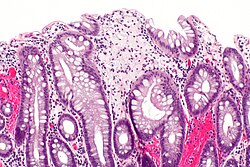

Xanthomatous polyp. H&E stain.

Xanthoma is a benign lesion due to the accumulation of lipid. It may be seen in association with hyperlipidemia.

It can be seen in numerous sites.

- Gastric xanthoma.

- Colorectal xanthoma.

- Urinary bladder xanthoma.[1]

- Hepatic xanthoma.[2]

- Esophageal xanthoma.[3]

- Others.